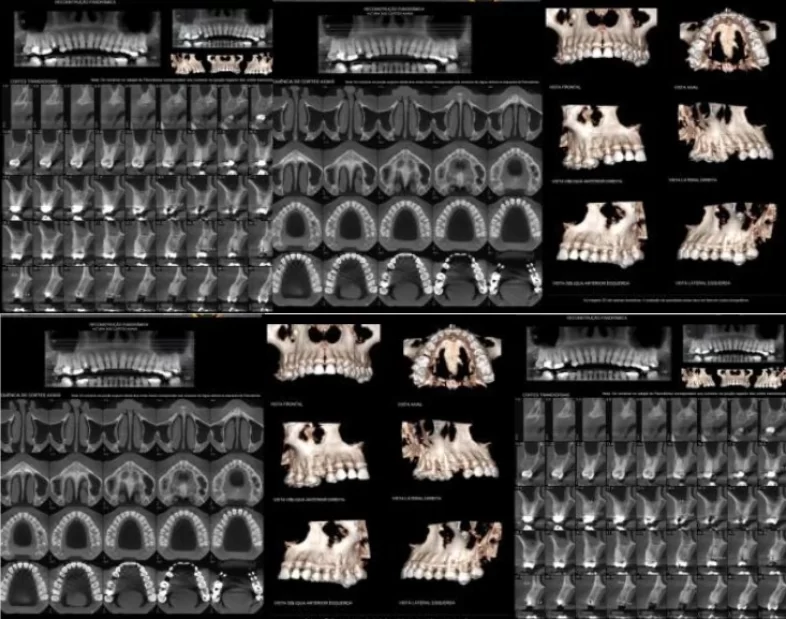

Tomografia Da Maxila

A tomografia da maxila, também conhecida como tomografia computadorizada da arcada dentária superior, é um exame de imagem que utiliza raios X e um computador para criar imagens detalhadas e tridimensionais (3D) das estruturas internas da maxila (osso da arcada superior). É uma ferramenta de diagnóstico avançado, amplamente utilizada na odontologia e em outras áreas médicas.

Os objetivos da tomografia da maxila são diagnosticar patologias, planejar tratamentos odontológicos e cirúrgicos, e avaliar a anatomia detalhada da região. A tomografia computadorizada (TC) de alta resolução, especialmente a de feixe cônico (Cone-Beam), fornece imagens tridimensionais (3D) que superam as radiografias convencionais, eliminando a sobreposição de estruturas.